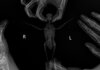

KatiKati спасибо Вам огромное, получилось!

IMG_6532.jpeg IMG_6531.jpeg